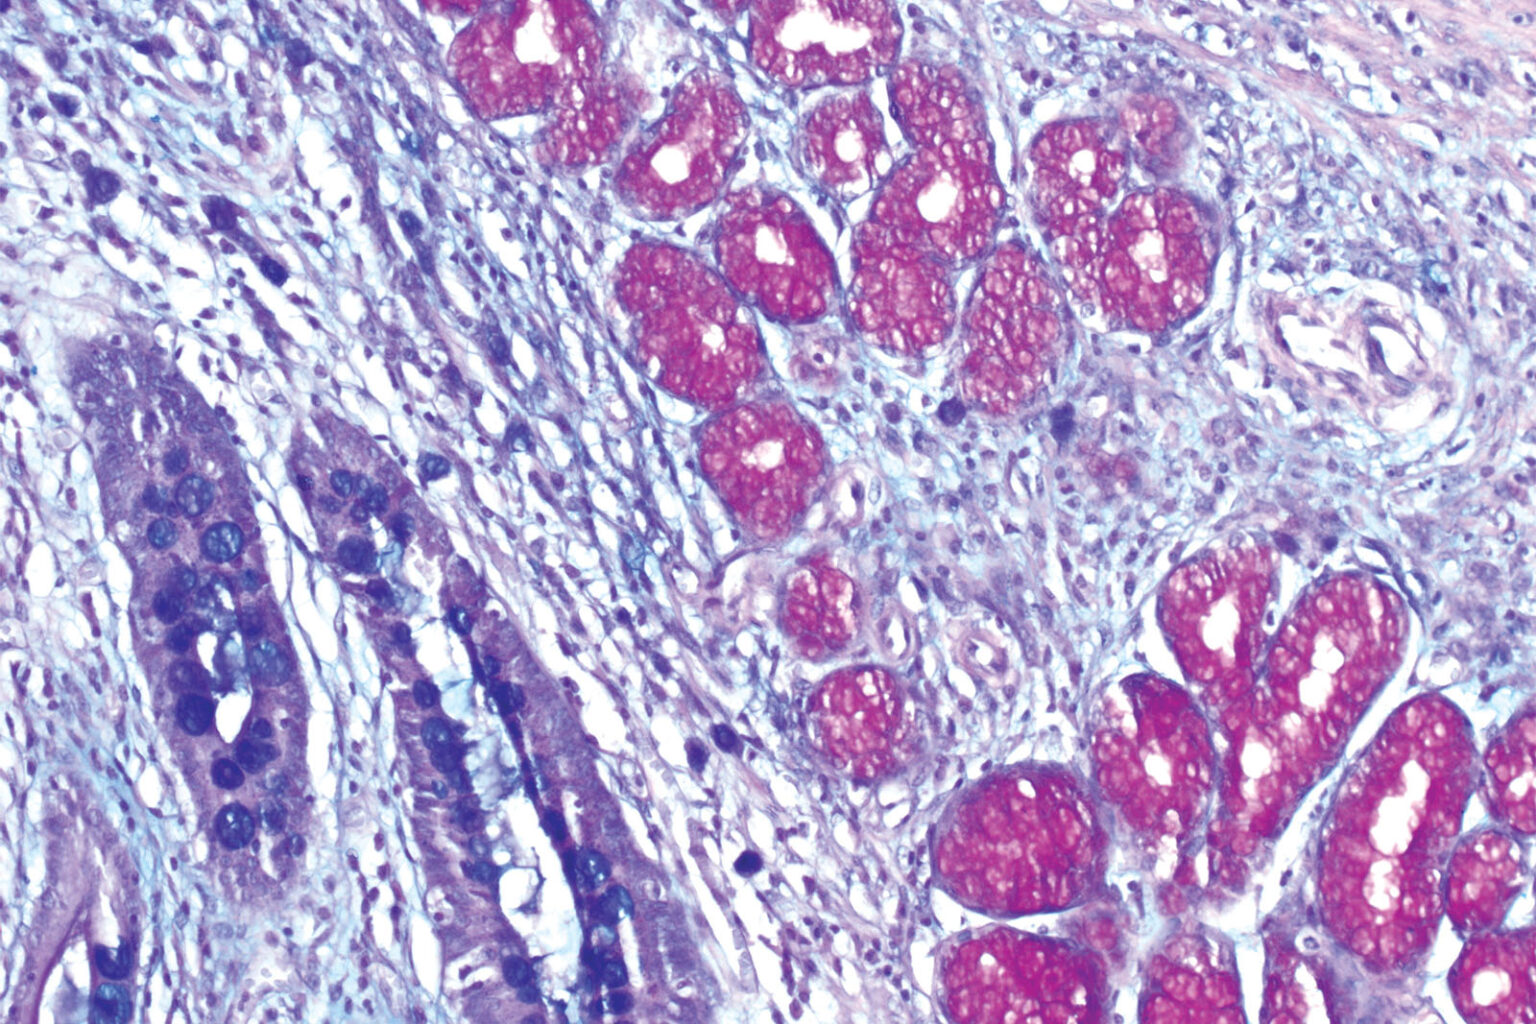

alcian blue staining troubleshooting -hyaluronic acid with alcian blue staining technique (15×) (human heart

-Hyaluronic Acid With Alcian Blue Staining Technique (15×) (human Heart

-Hyaluronic acid with Alcian blue staining technique (15×) (human heart www.researchgate.net